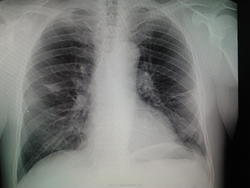

Мужчина 1956 г.р,проф.флг,жалоб со стороны легких не предъявляет,температура нормальная,посмотрела в амб.карте- последняя флг в 2008 году,там была норма,сейчас лечится у невролога по поводу межреберной невралгии.Можно ли расценить тень справа в тройке как фиброз?

С другой стороны тоже или фиброз, или дисковидный ателектаз. Возможно была пневмония с двух сторон. Наблюдение.

И здесь тоже, кажется, плохи дела, и опять в корне уже. А точно межреберная невралгия у него? И справа? Наводит на размышления. Поспрашивайте, если можно анамнез в ближайшие 3-5месяцев. Ничем не болел? Слева тоже изменения.

Замечание позволю. Если считаете, что лимфоузлы справа бронхопульмональные вовлечены, тогда и левые, вероятно, тоже увеличены...

Простите, тень обсуждаемая не в корне. Но лимфоузлы увеличенные могут быть в корне (или в корнях). За них скиалогия добавляет чутка.